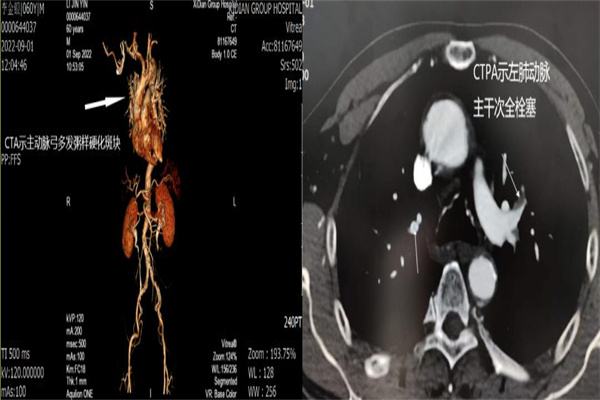

術(shù)后第3日,張爺爺再次發(fā)生腦栓塞,復(fù)查頭顱MRI提示雙側(cè)小腦半球新發(fā)急性腦梗死,經(jīng)多學(xué)科MDT討論后分析仍為心源性腦栓塞,且D-二聚體增高不排除肺栓塞,立即安排張爺爺完善CTPA、主動(dòng)脈CTA及床旁心臟彩超和雙下肢血管彩超檢查,結(jié)果提示張爺爺左肺動(dòng)脈主干次全栓塞、主動(dòng)脈多發(fā)粥樣硬化斑塊。

經(jīng)評(píng)估繼續(xù)給予抗凝治療,經(jīng)過1周左右的藥物鞏固治療,張爺爺?shù)牟∏椴胖鸩椒€(wěn)定,復(fù)查D-二聚體逐漸降至正常范圍?,F(xiàn)在,張爺爺已經(jīng)正常下地行走,身體也在漸漸恢復(fù)中。